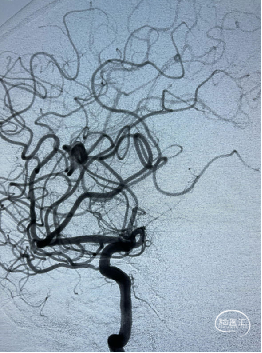

术后影像

术后多角度造影显示动脉瘤致密填塞,其他血管显影正常。术后CT无异常,mRS 0 分。

术后CT未见异常,mRS 0 分,无神经系统症状和体征,计划术后半年后复查DSA